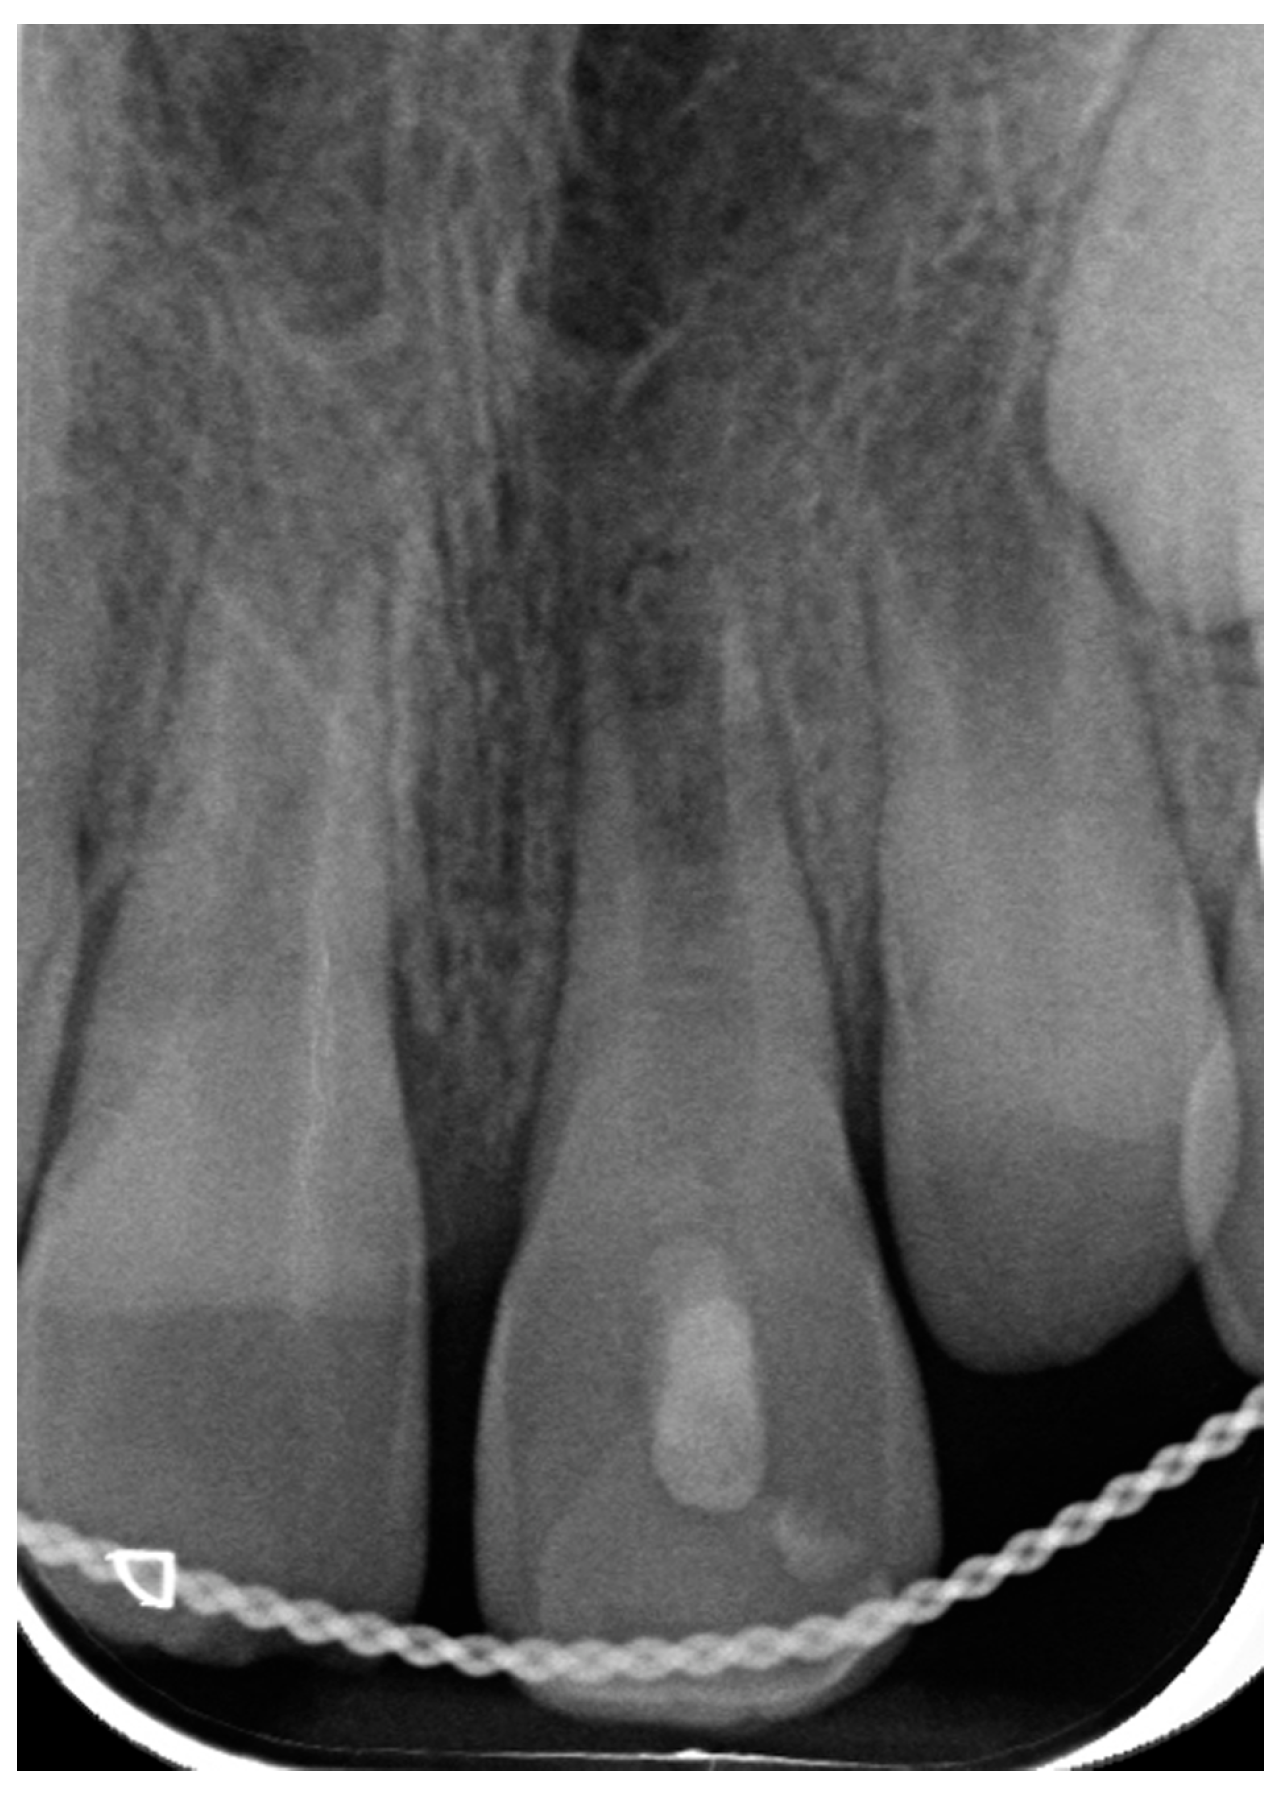

3.1. Case 1

- Dental history

- Clinical procedure

- Follow-up